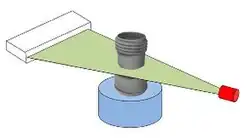

Die Gantry mit abgenommenem Gehäuse: „D“ markiert den Detektorkranz, bei „T“ befindet sich die Röhre (englisch Tube), die ihren Fächerstrahl in Richtung der roten Linien abgibt. „R“ markiert die Rotationsrichtung von Röhre und Detektor.

Die Gantry mit abgenommenem Gehäuse: „D“ markiert den Detektorkranz, bei „T“ befindet sich die Röhre (englisch Tube), die ihren Fächerstrahl in Richtung der roten Linien abgibt. „R“ markiert die Rotationsrichtung von Röhre und Detektor. -